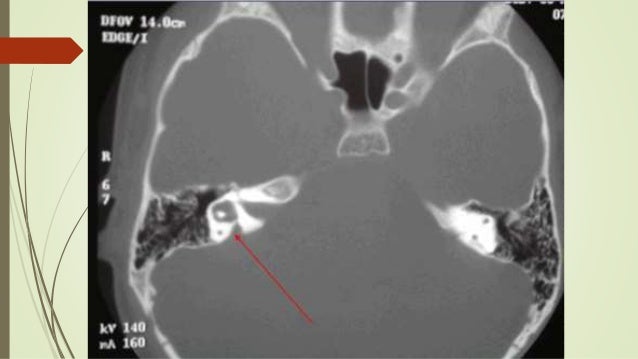

Ct Scan Temporal Bone Dr Zeeshan Ahmad

Ct scan temporal bone Dr Zeeshan Ahmad www.slideshare.net

temporal zeeshan